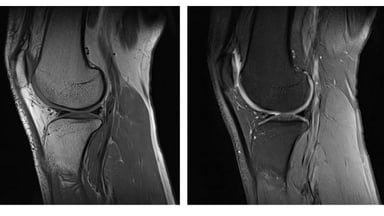

– Chụp xương khớp

– Các bệnh liên quan đến khớp gối, khớp vai, khớp khuỷu tay, khớp háng, cổ tay, cổ chân,…

Hình ảnh chụp MRI có giá trị cao giúp bác sĩ chẩn đoán chính xác bệnh lý gặp phải.